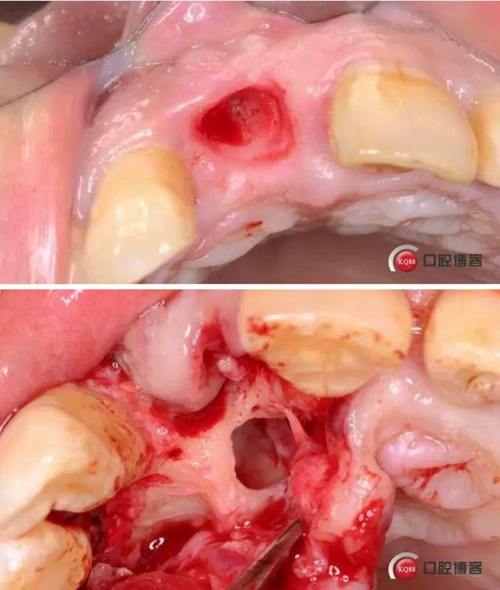

術(shù)中照